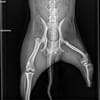

Abbo irrte wochenlang durch die Innenstadt, er war auf der Suche nach Fressbarem und Anschluss. Schliesslich lief er einfach zu uns in die Praxis. Ja, hier gab es eine kostenlose Kastration, aber das war in seinem Fall nicht ausreichend. Nicht nur, dass ihm die Hälfte eines Hinterbeines fehlte, auch sonst hätte solch ein kleines, freundliches Kerlchen kaum den Winter auf der Straße überstanden.

Abbo ist, trotz seines Handycaps, ein agiles, aufgewecktes Kerlchen. Er möchte seine Menschen gerne begleiten und viel erleben.